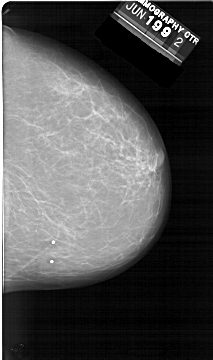

ics_version 1.0 filename A-1398-1 DATE_OF_STUDY 19 6 1992 PATIENT_AGE 62 FILM FILM_TYPE REGULAR DENSITY 2 DATE_DIGITIZED 9 9 1998 DIGITIZER HOWTEK 43.5 SEQUENCE LEFT_CC LINES 6526 PIXELS_PER_LINE 4201 BITS_PER_PIXEL 12 RESOLUTION 43.5 OVERLAY LEFT_MLO LINES 6871 PIXELS_PER_LINE 4186 BITS_PER_PIXEL 12 RESOLUTION 43.5 OVERLAY RIGHT_CC LINES 6466 PIXELS_PER_LINE 3826 BITS_PER_PIXEL 12 RESOLUTION 43.5 NON_OVERLAY RIGHT_MLO LINES 6871 PIXELS_PER_LINE 4021 BITS_PER_PIXEL 12 RESOLUTION 43.5 NON_OVERLAY |